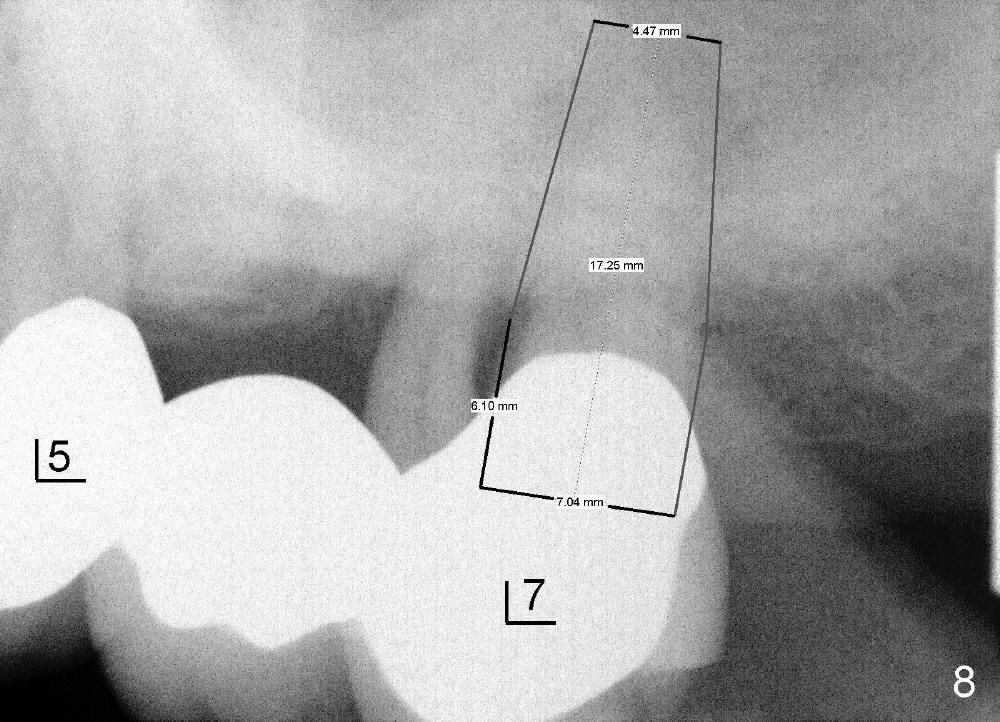

两周后郑先生也需要拔除左上第二磨牙即刻植牙(图八),植牙窝在中隔偏向颊侧开始(图七D蓝圆圈,与图七B对比),虽然植牙窝扩大过程中也逐渐向鄂侧移动,但是最后植牙基本落入拔牙窝中间(图七E粉红色圆圈,图九(术后四天),图十(术后一个月),图十一(三个月;第一磨牙植牙一周))。